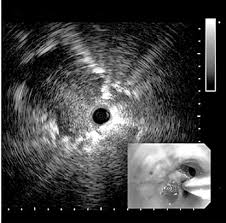

Saiba maisUltrassonografia Endobrônquica (EBUS)

Ultrassonografia Endobrônquica é uma broncoscopia com ultrassom para avaliação do sistema respiratório

Ultrassonografia Endoscópica (EUS)

A ultrassonografia Endoscópica (EUS) ou ecoendoscopia é um procedimento médico em que a endoscopia digestiva é combinada com ultrassom para obter imagens e guiar biópsias dos órgãos internos do tórax e abdômen.